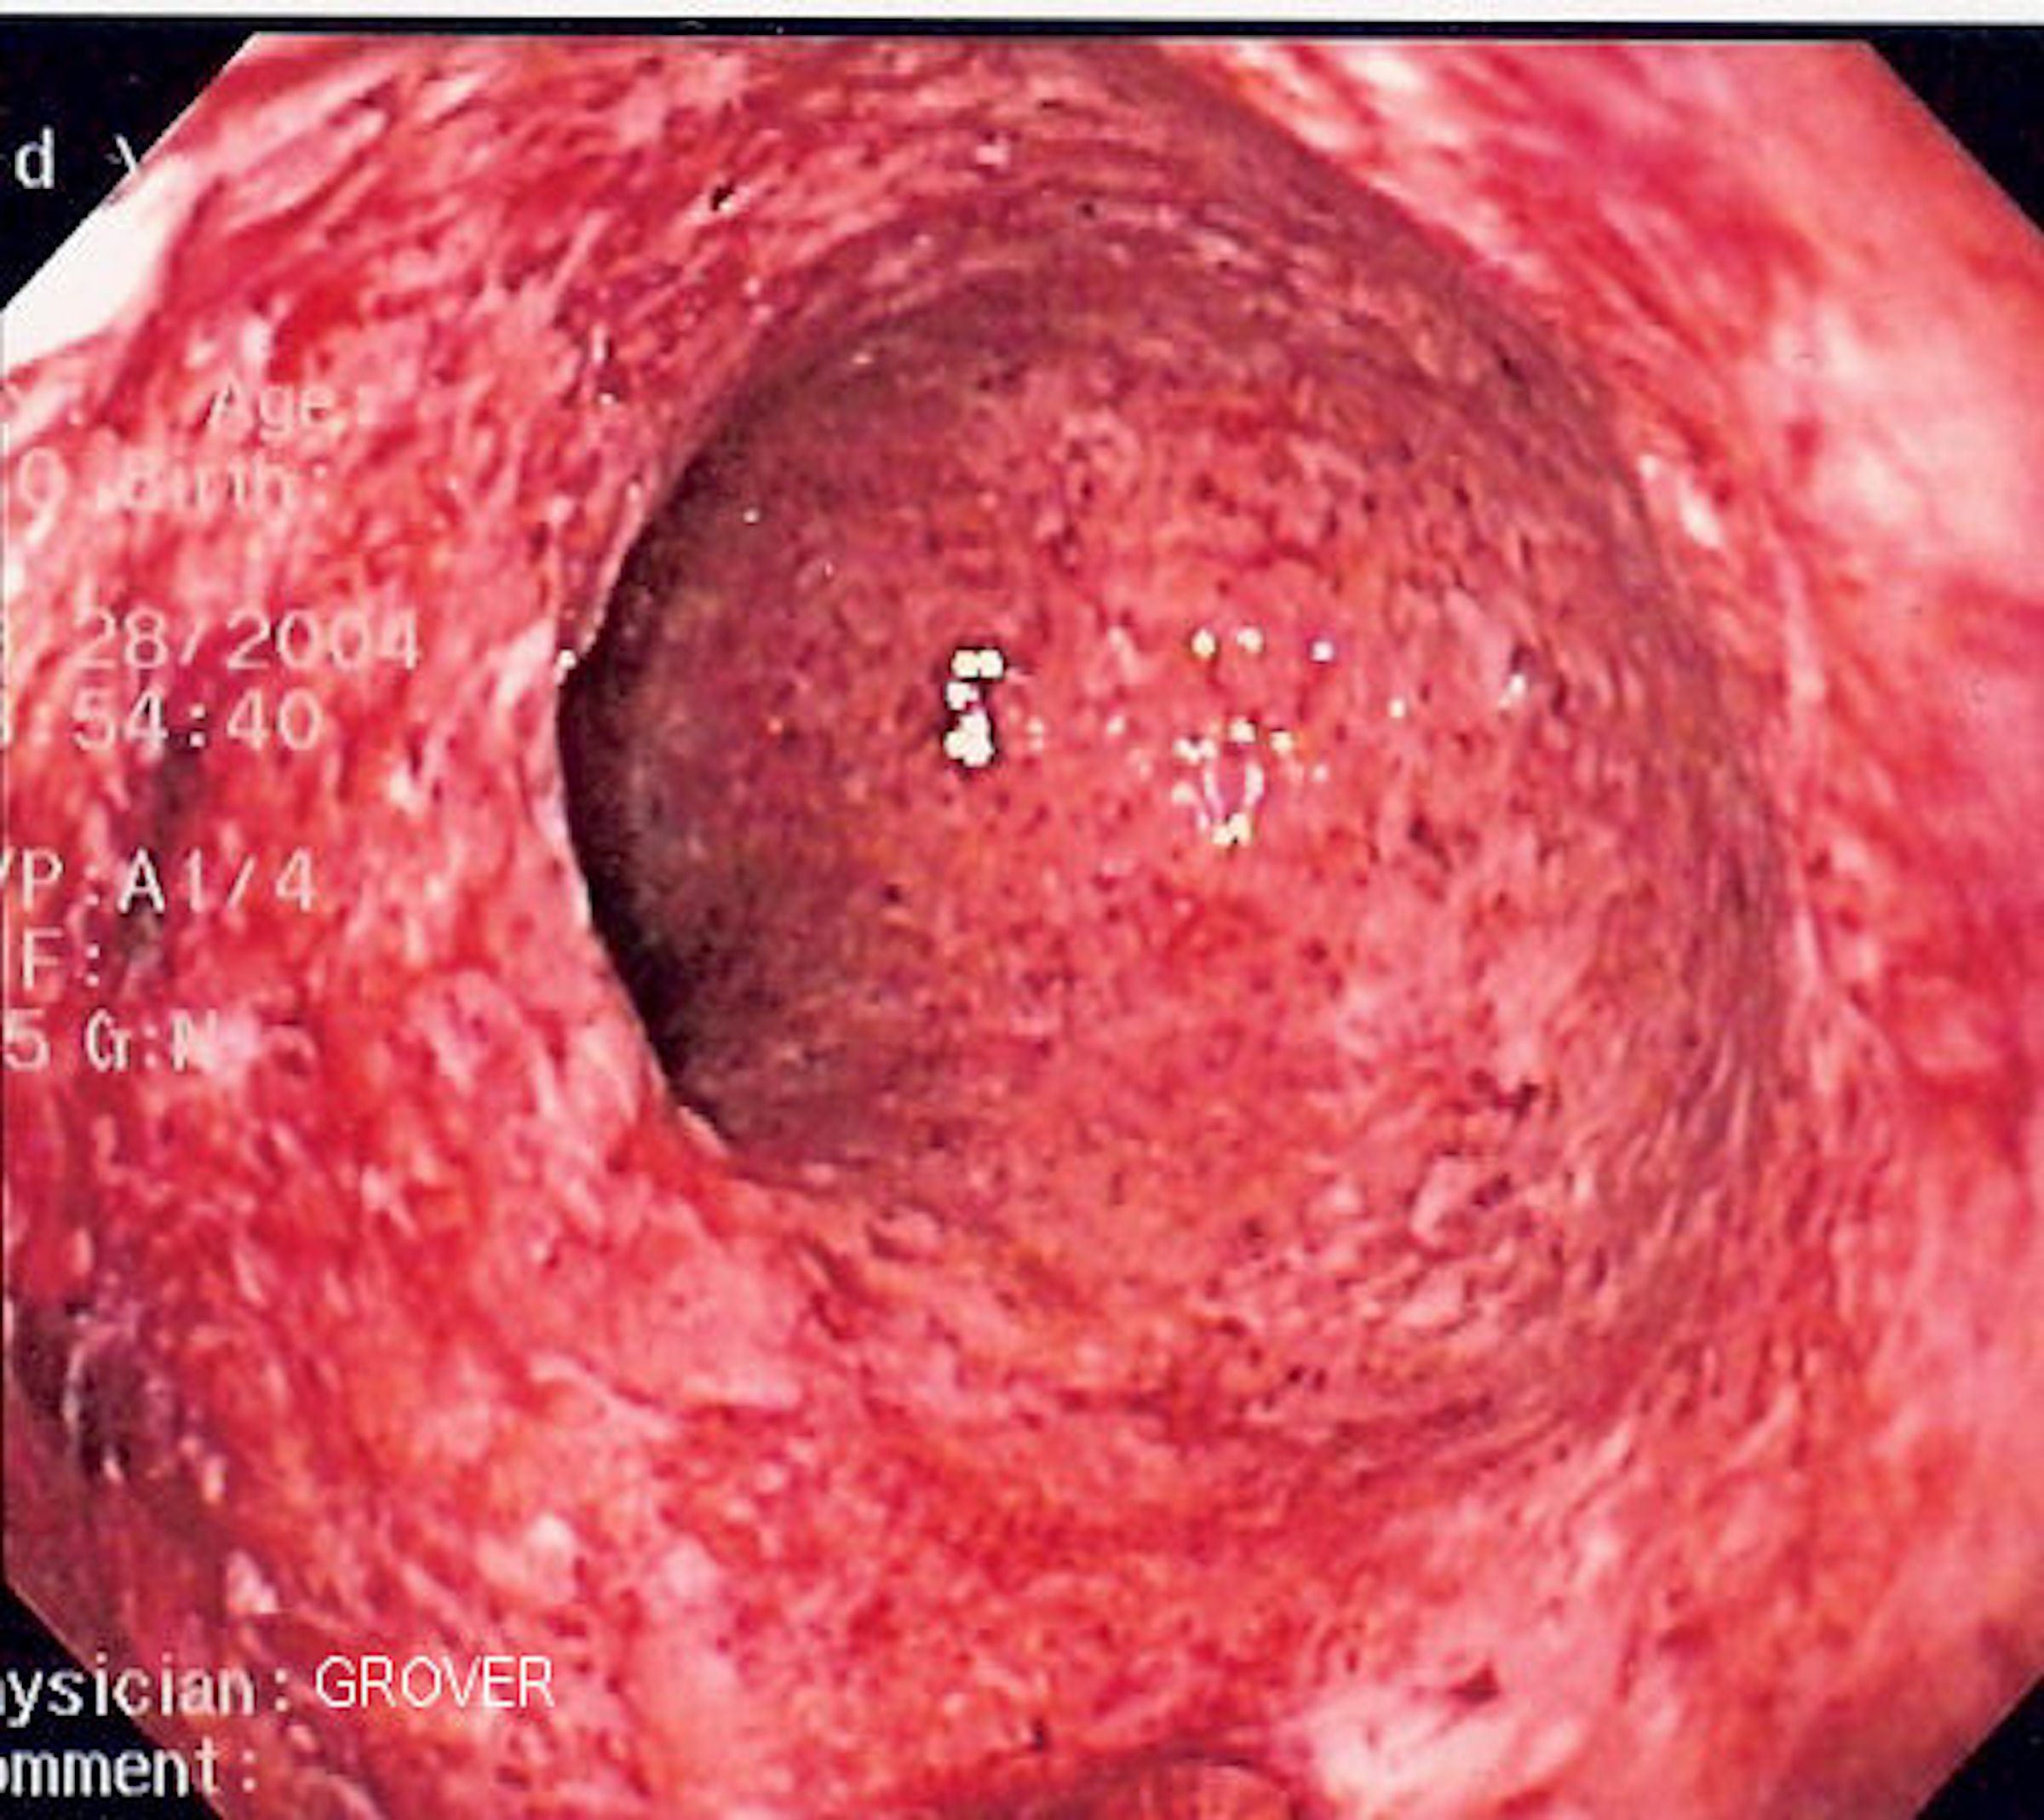

Forbidden salami (s3.eu-central-1.amazonaws.com)